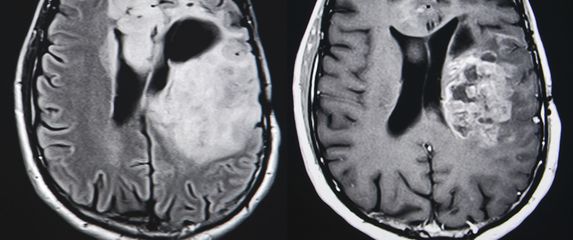

i anketa Revolucionarna ideja Znanstvenici testiraju kapi za nos koje izravno napadaju jedan od najopakijih tumora